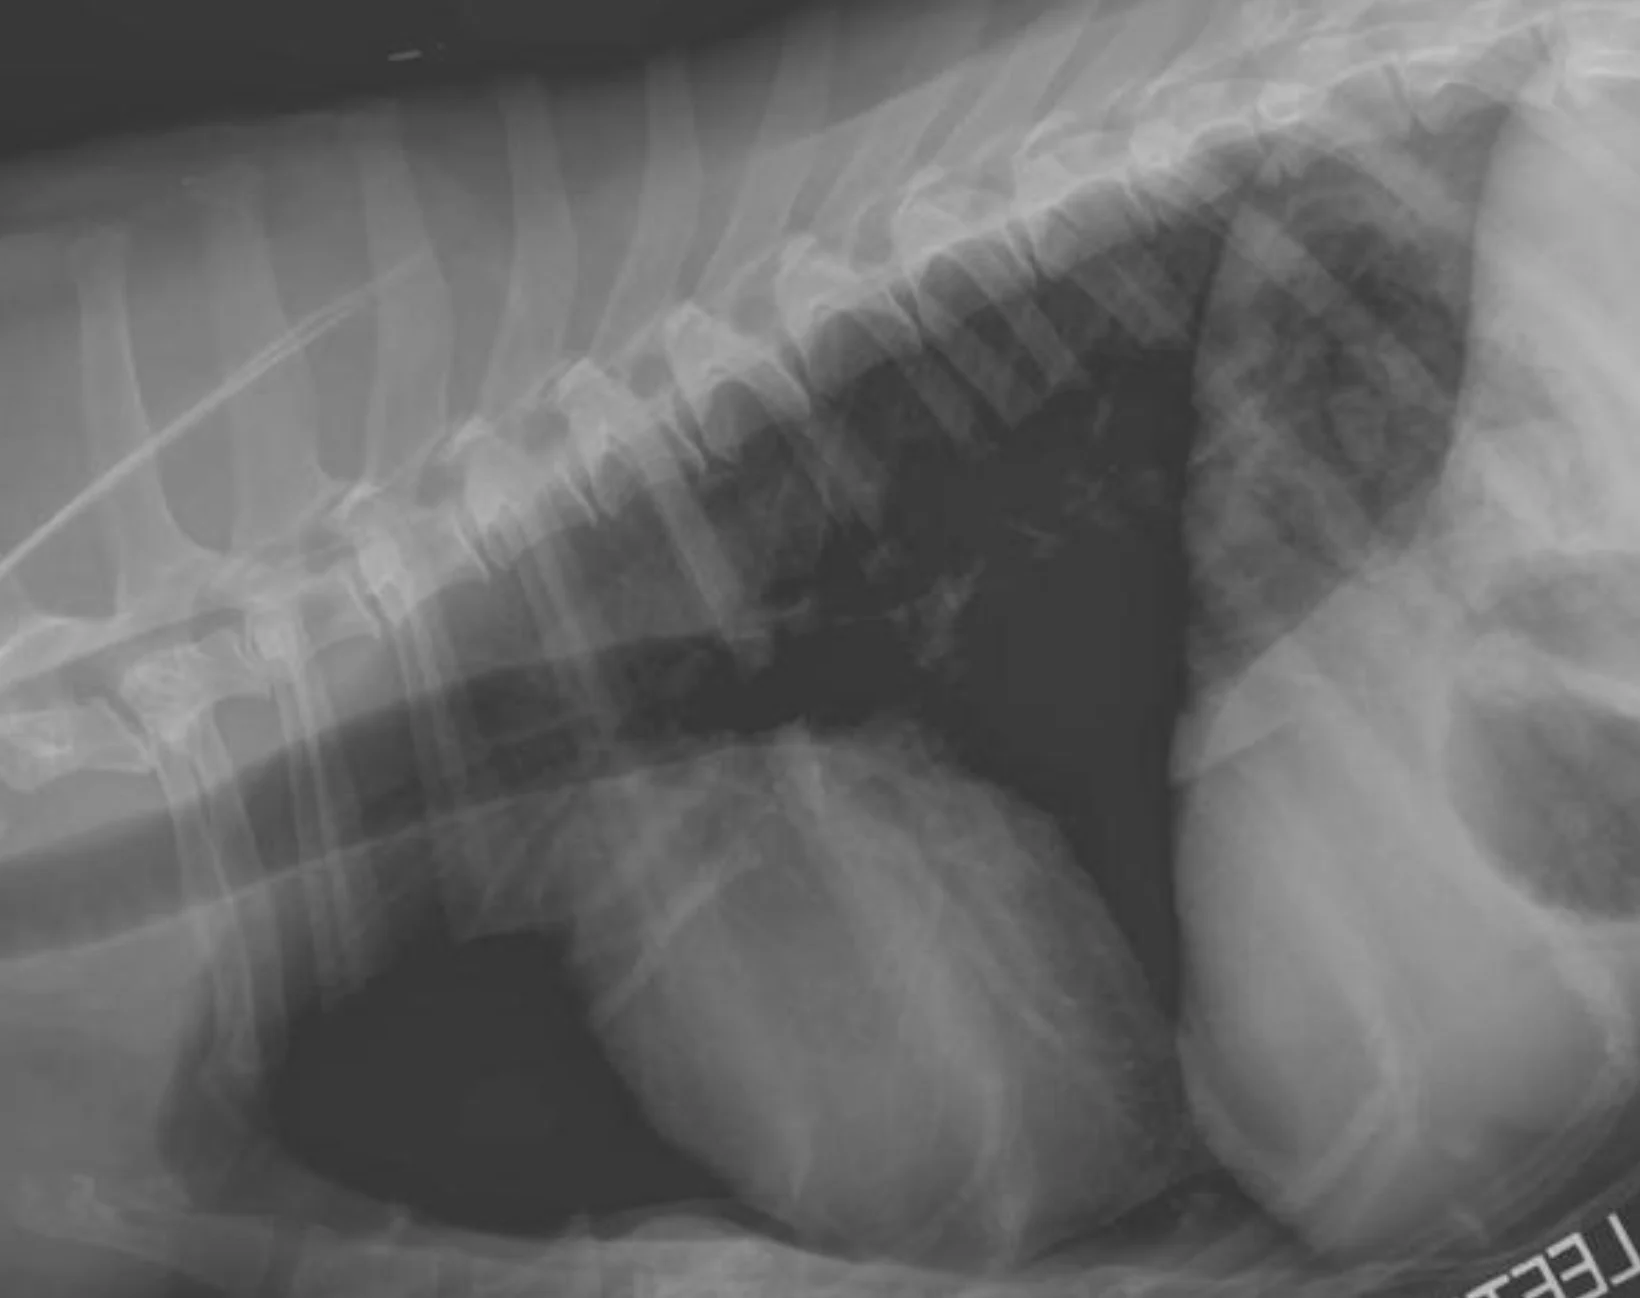

If you are using a digital radiography system, the software attempts to adjust brightness to correct for over- and underexposure. If a digital image is severely underexposed, however, the digital system cannot correct for it. The resulting image will look very grainy, as in this example of a cat thorax that was extremely underexposed (Figure A). Figure B shows the corrected technique.

In most cases, an overexposed radiograph will have soft tissue that cannot be seen, even with adjustments in brightness (window/level). In Figure C, the digital image is overexposed, which results in inability to see the lung in the cranioventral thorax and between the heart and diaphragm; this area will remain black with increases in brightness. The technique has been corrected in Figure D.